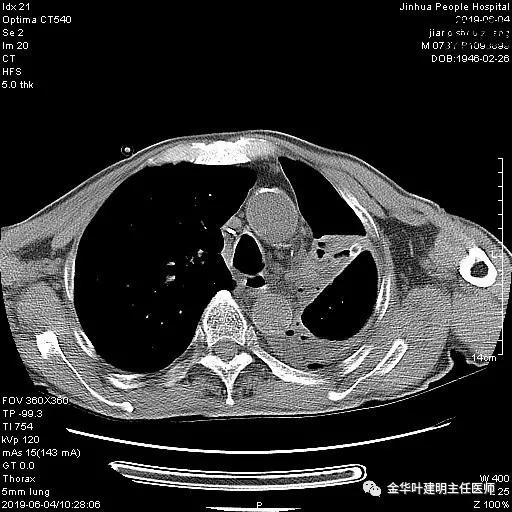

考虑左侧大量胸腔积液,遂进一步胸部CT检查:

以上是肺窗表现,下面为纵隔窗影像: